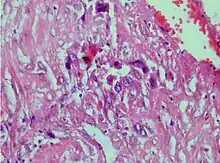

| Photomicrograph showing proliferating intermediate trophoblast with scarce cytotophoblastic and syncytiotrophoblastic elements | |

A placental site trophoblastic tumor is a monophasic neoplasm of the implantation site intermediate trophoblast, and usually a benign lesion, which comprises less than 2% of all gestational trophoblastic proliferations. Preceding conditions include molar pregnancy (5%). Compared to choriocarcinoma or invasive mole, hemorrhage is less conspicuous and serum β-HCG level is low, making early diagnosis difficult.